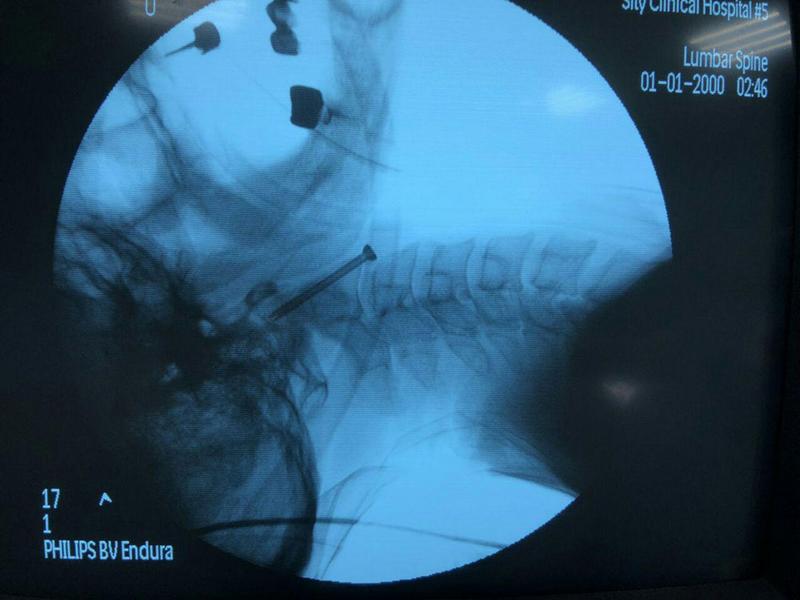

Такую операцию всего несколько дней назад провели Владимиру. Житель Запорожья поступил в нейрохирургическое отделение 5 горбольницы после ДТП с переломом зубовидного отростка второго шейного позвонка. Медики отмечают, что раньше в такой ситуации пациенту предстояла серьезная операция по установке объемной фиксирующей конструкции. В результате, несколько позвонков становились неподвижными, а движения в шейном отделе были ограничены. Нейрохирурги 5 горбольницы пошли другим путем: применили новейшую технологию и решили проблему с максимальными преимуществами для пациента.

"Мы выполнили остеосинтез перелома, зафиксировав отломки всего одним компрессионным винтом. Благодаря такому вмешательству пациент сможет полностью восстановиться и вернуться к прежнему уровню активности без ограничений. Кроме того, такая операция малотравматичная – пациент может вставать с постели уже на следующий день после вмешательства, а спустя еще два дня выписывается домой. Таковы тенденции современной хирургии – стремление к максимальной малотравматичности и миниинвазивности", - прокоментировал Дмитрий Ивахненко, заведующий отделением нейрохирургии Запорожской городской больницы экстренной и скорой медицинской помощи.

Такую операцию можно считать филигранной – специалистами была проведена очень тонкая работа, ведь в этой зоне очень важно зафиксировать позвонки, не задев жизненноважные структуры головного и спинного мозга. Главное подтверждение профессионализма и блестящей работы команды врачей – счастливый пациент, который уже готовится к выписке.